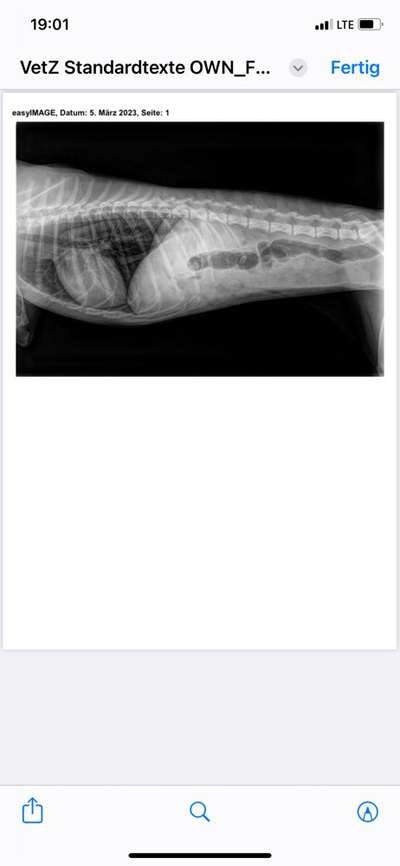

Also sie hat jetzt was gegen Übelkeit gespritzt bekommen und wir haben ein Röntgenbild machen lassen. Auf dem sieht man wohl, dass der Magen und Darm entzündet ist. Der Arzt meint das kann nicht nur von den giardien kommen und dass wir mit unserer Tierärztin nach der Ursache suchen müssen.

Hier das Bild. Mir sagt es nix aber ich bringe es morgen meiner Tierärztin.